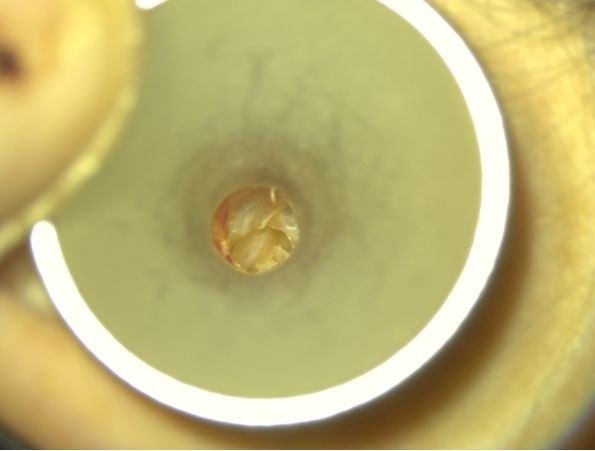

Bogata w płytki i leukocyty fibryna jest stosowana w regeneracji tkanek od ponad 15 lat. Pozytywny wpływ PRF (platelet-rich fibrin) na regenerację tkanek miękkich jest niewątpliwy, bezsporny i częściowo udowodniony w badaniach klinicznych i analizach biochemicznych. Wpływ PRF na regenerację tkanki kostnej jest obserwowany klinicznie, ale nadal niedostatecznie poznany jest mechanizm tego zjawiska.

Platelet- and leukocyte-rich-fibrin has been used in regeneration of tissue for more than 15 years. The positive influence of PRF on the regeneration of soft tissue is undoubtedly, without question and partially proven in clinical studies and biochemical analysis. Influence of PRF on regeneration of bone tissue is observed clinically but the mechanism of this phenomenon is still not sufficiently known.